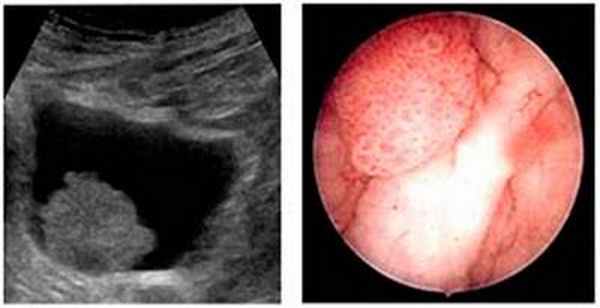

Ведущим методом диагностики рака мочевого пузыря является цистоскопия. Метод заключается в осмотре полости мочевого пузыря. При цистоскопии можно оценить состояние слизистой мочевого пузыря, размеры, количество, локализацию, внешний вид, распространенность опухоли, а также вовлеченность устьев мочеточников.

УЗИ мочевого пузыря и почек, при котором можно визуализировать саму опухоль и состояние верхних мочевых путей.

На сегодняшний день основной метод диагностики опухоли мочевого пузыря – цистоскопия (осмотр слизистой мочевого пузыря «изнутри» с помощью специального прибора - эндоскопа), позволяющая не только увидеть опухоль, но и взять кусочек новообразования для гистологического исследования. Основной недостаток данного метода, сильно ограничивающий его применение, – известная инвазивность (дискомфорт для пациента).